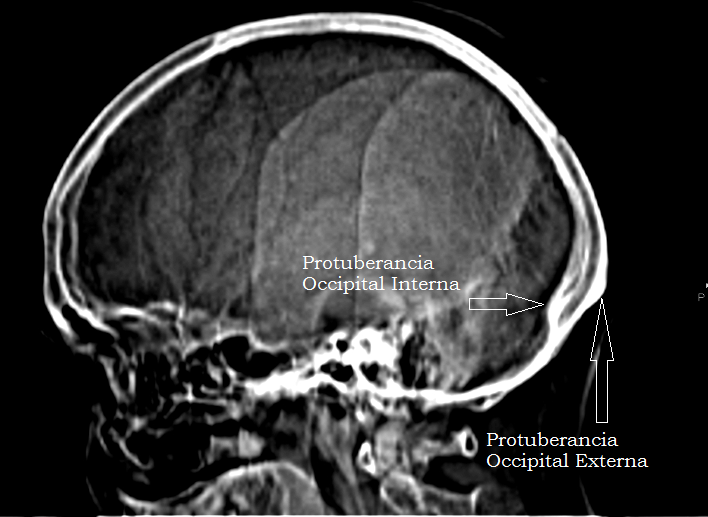

External occipital protuberance (Protuberantia occipitalis externa from www.pinterest.co.kr

External occipital protuberance (Protuberantia occipitalis externa